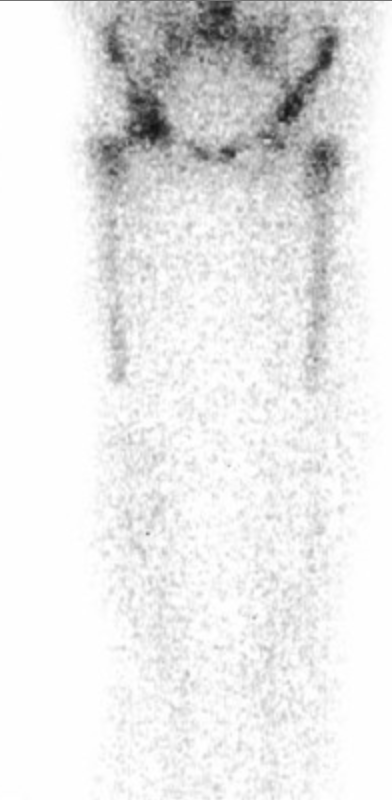

Shin Splints (Medial tibial stress syndrome)

• Seen as diffuse uptake in the posterior-medial tibial cortex

• Best visualized on the delayed static images

• Note: stress fracture will typically have early uptake

• Arterial and blood pool images are normal